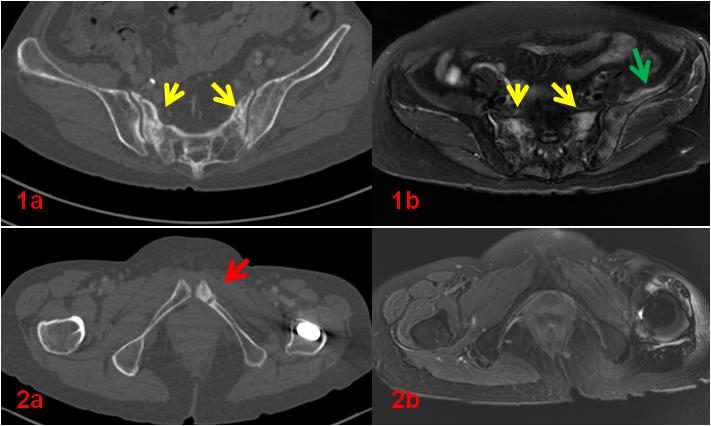

老年女性,1年前因直腸惡性腫瘤于外院行放射治療,此次常規(guī)復(fù)查平掃CT示骶骨及左側(cè)恥骨密度不均勻,左側(cè)恥骨骨質(zhì)斷裂;平掃M(jìn)R示雙側(cè)骶骨翼、左側(cè)髂骨及左側(cè)恥骨異常信號(圖1、2);為進(jìn)一步明確診斷行全身骨顯像ECT檢查(圖3)。

圖1、2初診CT、MR影像。CT示骶骨密度不均勻增高(1a,黃箭),同部位MR顯示壓脂信號增高(1b,黃箭),同時(shí)顯示左側(cè)髂骨及周圍軟組織壓脂信號增高(1b,綠箭);左側(cè)恥骨骨質(zhì)斷裂(2a,紅箭)。